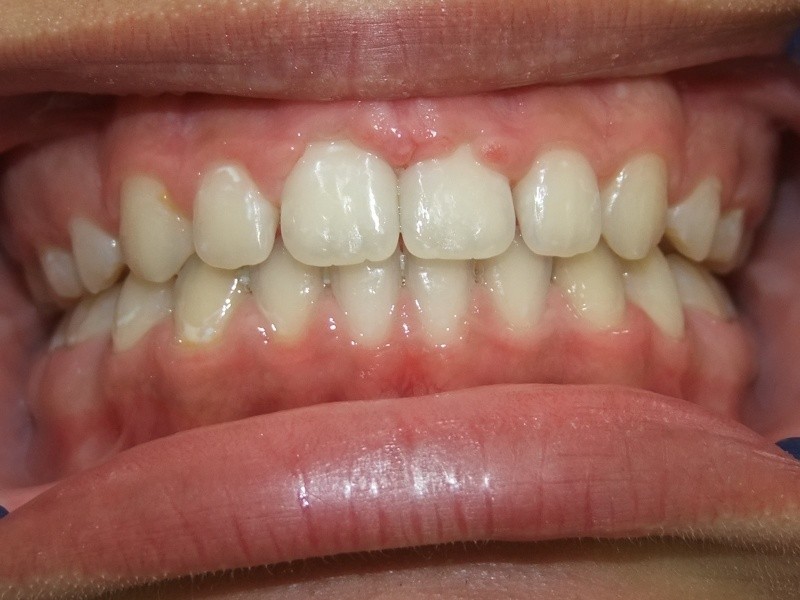

eindfoto

Beschrijving

Leeftijd bij aanvang: 9 jaar

1-6 maanden Bonded Hyrax in de bovenkaak, banden/slotjes in de onderkaak met Transforce

7-13 maanden: Twinblock

14-47 maanden: Volledig banden/slotjes in de boven-en onderkaak (omdat er hier blijvende kiezen ontbraken moesten er kiezen getrokken worden en de ontstane ruimtes gesloten, dit verklaart de langere behandeltijd)

Retentie fase: Wrap en C-CBar